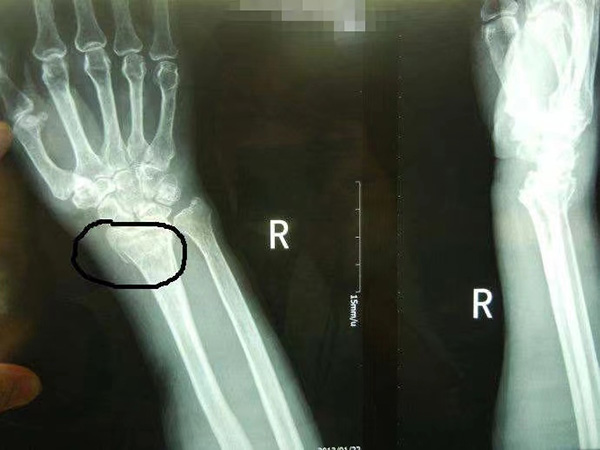

橈骨遠(yuǎn)端骨折是指發(fā)生在距橈骨遠(yuǎn)端關(guān)節(jié)面3cm以內(nèi)的骨折。

1. 臨床表現(xiàn):伸直型骨折即Colles骨折,多由間接暴力引起。傷后局部隨即出現(xiàn)腫脹、疼痛,可有典型畸形姿勢,側(cè)面呈“餐叉”樣畸形,正面呈“槍刺樣”畸形。查體局部壓痛明顯,可觸及骨擦音和異常活動,腕關(guān)節(jié)活動障礙,皮下出現(xiàn)瘀斑。

1. 臨床表現(xiàn):即Smith骨折。它的致病因素除了間接暴力外,直接暴力打擊腕部也是致病誘因,查體局部有明顯壓痛,尺橈骨莖突關(guān)系異常,與伸直型骨折移位方向恰好相反,又叫反Colles骨折,可伴有尺骨莖突骨折,很少有嵌入骨折。